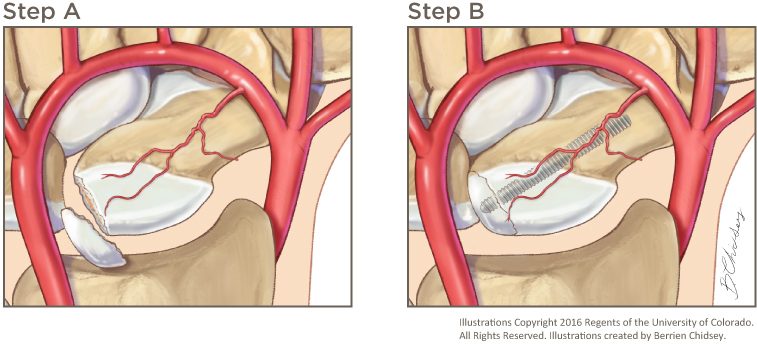

- 만약 전위가 있거나 근위부 골절인 경우는 수술을 시행합니다.

- 골절이 주상골(근위부)의 맨 끝에서 발생된 경우

- 조각 사이에 틈이 있는 경우(전위)

- 파편이 2개 이상일 때(분쇄)

- 골절선이 매우 비스듬한 경우

- 주상골이 3-6개월 내에 치유되지 않는 경우(주상골 불유합)